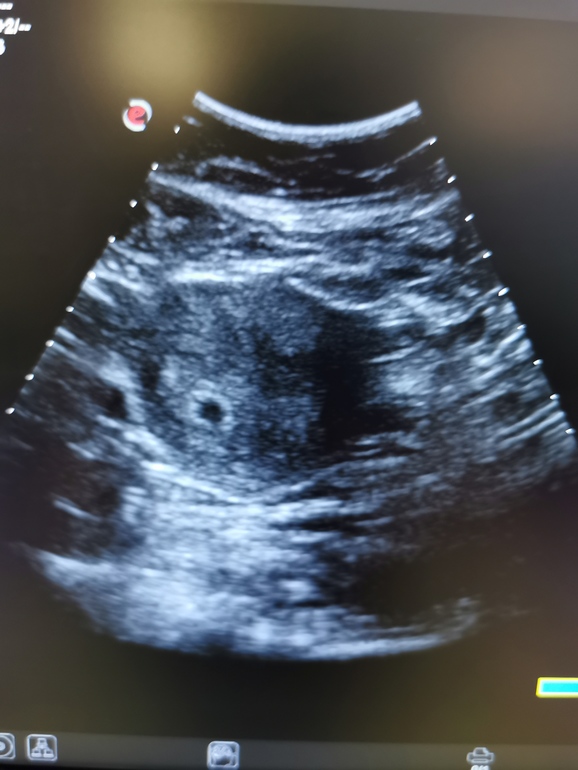

Официально беременна 🤗

Всем привет. Неделя мучения, после того, как яйцо в ту среду не нашли из за маленького срока. 100 мыслей... Сегодня было контрольное.

мы на месте. Теперь ждём 12 недель, если ничего не будет беспокоить. Я выдохла немного. Спасибо богу за такой подарок.